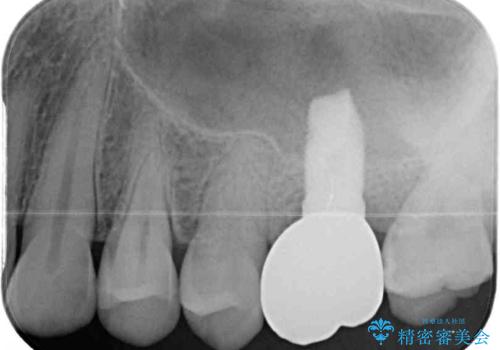

破折した場合にはインプラントを埋入した上で補綴治療を行うこととしました。

詰められた材料や壊死した組織を除去したところ、鮮明な破折線が認められたため、速やかに抜歯し、傷や骨の治癒を待って、サイナスリフトにより骨高さの低い部分にインプラント埋入を行いました。